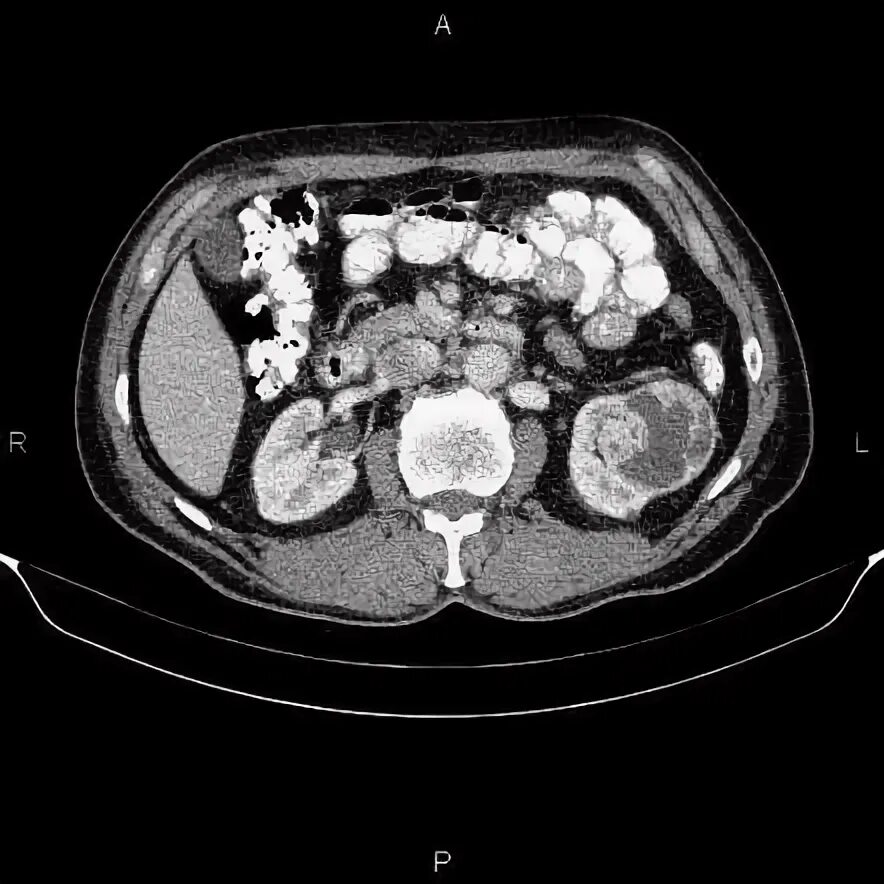

Кисты почек bosniak